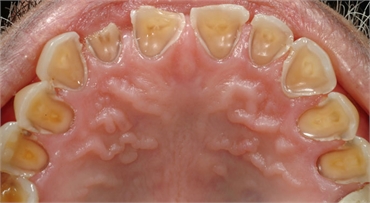

The stomach acid from GERD can eat away the enamel on teeth. Enamel is the outermost layer of teeth meant to protect the soft and sensitive inner layers. The pattern of erosion from acid reflux often starts with the back teeth and the inside surfaces of teeth. But in some cases, the chewing surfaces of the teeth can also suffer damage. Unfortunately, enamel loss is permanent and can increase the risk of dental decay.